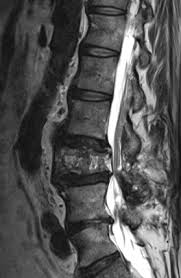

These levels were investigated in this study as degeneration occurs most often and earliest in these three lower vertebral levels 17 fourth and fifth lumbar spine vertebrae and the first sacral vertebra were evaluated for disc bulging and protrusion See Lumbar Artificial Disc Replacement for Chronic Back Pain A high intensity zone HIZ is seen at L4-L5 Depending on the extensiveness. Es wurde eine ausgeprägte Osteochondrose mit Pseudolisthese und Bandscheibenprotrusion L45 diagnostiziert. Bei einer Bandscheibenprotrusion können die Nervenwurzeln hier blau geschädigt werden.

Protrusion L4 5 Bandscheibenprotrusion L4 L5 Mrt Lws